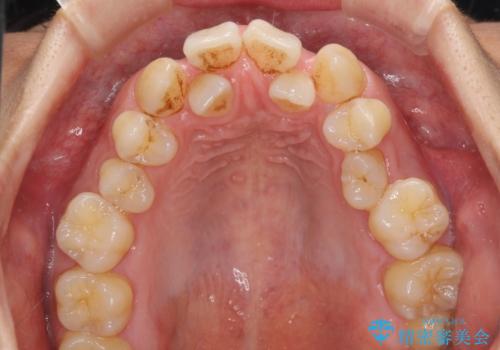

- 前歯の著しいデコボコを気にして来院された患者様です。

上顎の左右側切歯(前から2番目)が裏側に隠れいてる状態で、咬み合わせや清掃性に大きな問題が認められました。

叢生が著しいため、上下左右の小臼歯4本を抜去し、目立たないワイヤー装置にて矯正治療を行うこととしました。